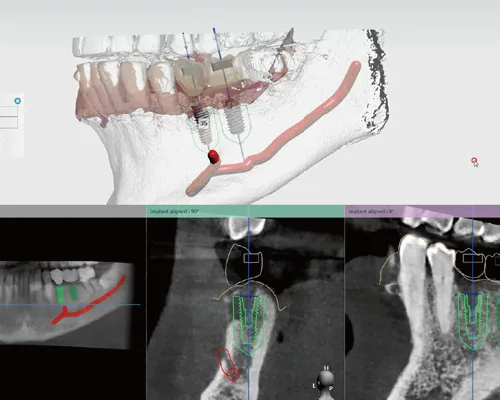

- ③インプラントシュミレーション

当院ではガイデッドサージェリーという治療方法でインプラントを行います。

ガイデッドサージェリーとは最終的にどういうインプラントをどの位置にどの角度で埋め込むかという計画をコンピュータ上で事前にシュミレーションを行ない、手術はシュミレーションを行なったプラン通りにインプラントを埋め込むためのマウスピースを利用して行うという安心で安全な手術方法です。

最終的にインプラントの上に綺麗にケアしやすい被せ物が装着できるように精密な治療計画をプランニングします。

当院のインプラント処置は安全に確実に痛みや腫れを少しでも減らすためにガイデッドサージェリー(ワンガイドシステム)という方法を用います。

ワンガイドテンプレート手術とは?

- デジタルシミュレーションの画像より正確な診断を行う

- デジタルシミュレーションで手術部位のインプラントを埋入する位置を決定してワンガイドテンプレートの位置の確認と製作をする

- ワンガイドテンプレートが正確な位置であるため、安全に早くインプラント手術ができる

ワンガイドシステムとは?

STEP2

- デジタルシミュレーション画像で位置方向を決める

- デジタルシミュレーション画像でワンガイドテンプレートを製作